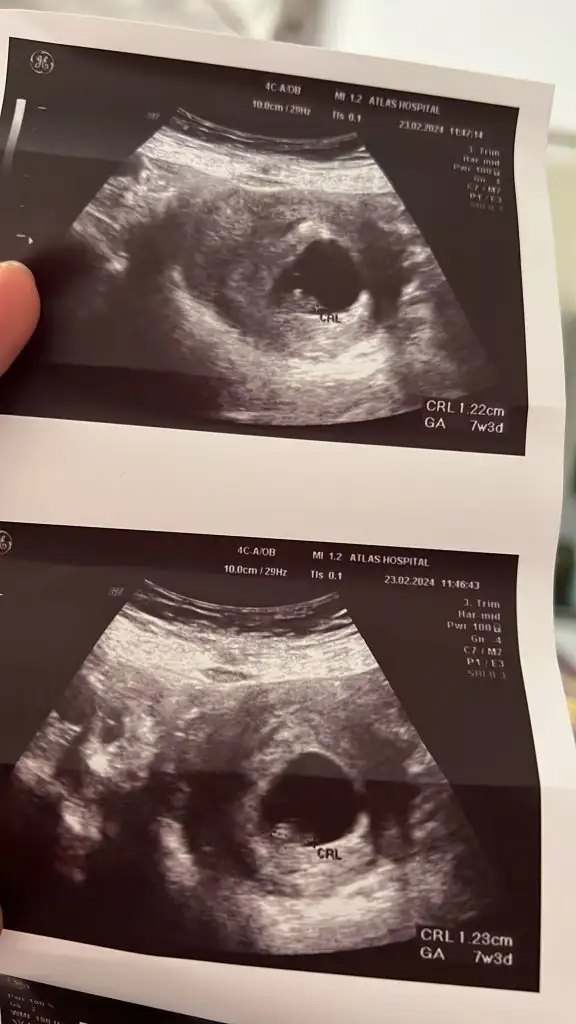

Banada yorum yaparmisiniz acaba ilk foto 13+6 Ken olan ulturoson resmi ikincide 6+7 haftalık ulturoson resmi şuan ,16 haftaligiz fktotumuz hala cinsiyet söylemedi